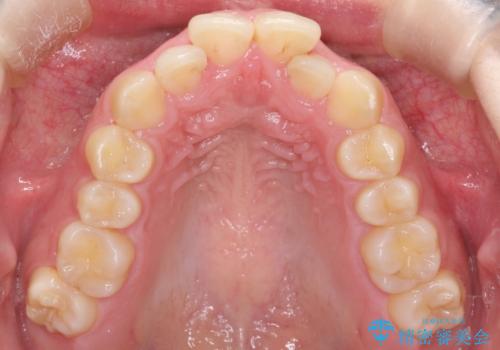

インビザラインでの前歯のガタガタの矯正

- 上下の前歯のがたつきを主訴に来院されました。

歯と歯の間をわずかに削りスペースを作り、インビザラインにて矯正治療を行うこととしました。

使用時間を守っていただけたので、スムーズに矯正を終了することができました。